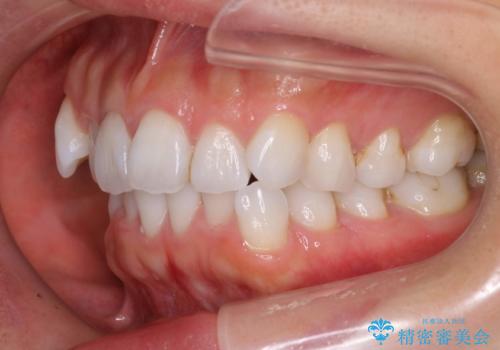

抜歯せずに八重歯のマウスピース矯正

- 1年3ヶ月

- 非抜歯・遠心移動+IPR+拡大 によるマウスピース矯正を計画した。

八重歯がシビアな場合、抜歯をしないと治せないケースもありますが、奥歯の位置関係を修正したり、歯のサイズダウンを行うことで、抜歯をせずに改善できる場合もたくさんあります。